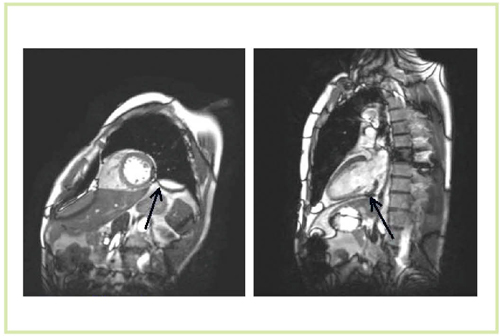

3T MRIによる心臓は,susceptibility artifactの影響やSAR(specific absorption rate)の制約のために,従来は撮像が困難な領域であった。しかし,Titan 3Tでは非常に明瞭な画像が得られている(図5〜8)。

図5 急性心筋梗塞症例(60歳代,男性)のT2強調画像 (脂肪抑制black blood TSE)(Titan 3T) SNRや浮腫心筋,正常心筋のCNRが向上

図5 急性心筋梗塞症例(60歳代,男性)のT2強調画像

(脂肪抑制black blood TSE)(Titan 3T)

SNRや浮腫心筋,正常心筋のCNRが向上